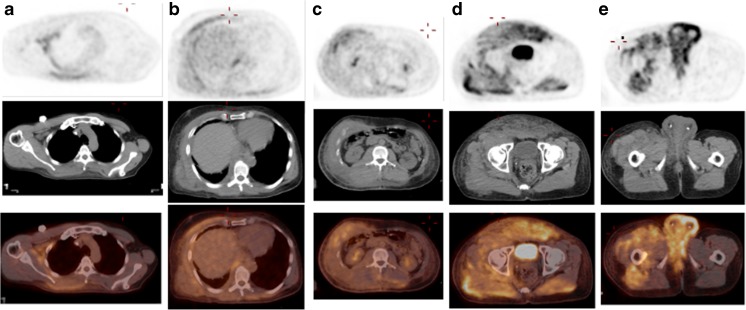

Fig. 1.

a Post-surgery and chemo-radiation restaging PET MIP image demonstrates active tumor in the right lung apical pleura extending into the chest wall. Probably active metastases of the mediastinal and hilar lymph nodes (not shown). Mild FDG uptake in the right lower thorax and flank favors representing post-surgical changes without evidence of local recurrence. b Post-chemoradiation restaging PET MIP image demonstrates an interval decrease of FDG avidity of the right apical pleural tumor and thoracic lymphadenopathy. No evidence of recurrence in the right lower thorax. c Post-palliative chemotherapy restaging PET MIP image demonstrates extensive and intense hypermetabolic metastatic mesothelioma in the skin, subcutaneous tissue and musculature involving the right neck and bilateral chest, abdomen, pelvis and thighs, right greater than left. The most active disease is in the bilateral scrotum and perineum with concern for possible involvement of the testicles and rectum. Right pleural tumor and mediastinal lymph nodes are stable

Fig. 2.

a, b, c, d Post-palliative chemotherapy restaging PET (from the same PET exam on Fig 1. c) axial attenuation corrected PET, non-contrast CT and fusion images at the levels of axilla, lower thorax, mid abdomen, pelvis and perineum show no pleural or peritoneal metastasis and tumor spread in the skin, subcutaneous tissue, musculatures and possible testicle and rectum involvement